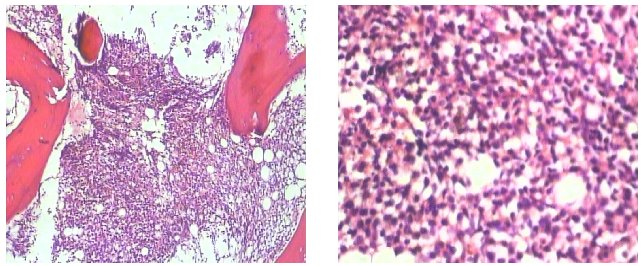

右側(cè)胸壁病理診斷

鏡下描述:腫瘤由小圓細(xì)胞構(gòu)成,呈片狀彌漫性排列,浸潤性生長,累犯至真皮下纖維脂肪組織及橫紋肌組織。

病理診斷:「右胸壁」小圓細(xì)胞惡性腫瘤,淋巴造血系統(tǒng)腫瘤首先考慮,結(jié)合免疫組化考慮粒細(xì)胞肉瘤;該病例經(jīng)上級醫(yī)院病理專家討論。

鏡下所見: